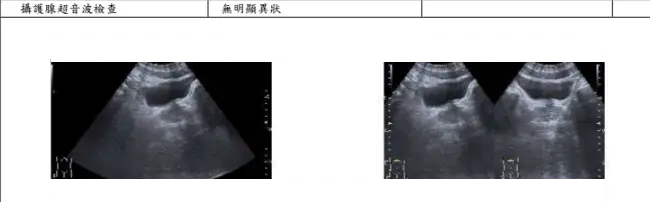

kawazakiz2: 體檢的超音波沒問題喔

https://i.meee.com.tw/ZjTH0VF.png

9月才做的23F 10/09 13:07

[圖]